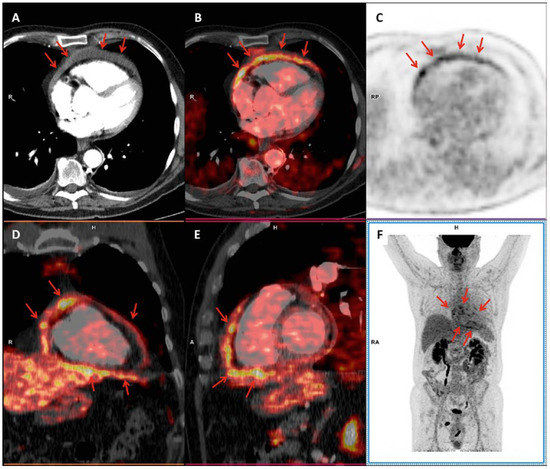

A "Ring of Fire" Around the Heart: Pericarditis Detected by FDG-PET/CT

by Giorgio Treglia, Mariana Raditchkova, Luca Ceriani and Luca Giovanella

Cardiovasc. Med. 2018, 21(9), 234; https://doi.org/10.4414/cvm.2018.00576 - 19 Sep 2018

Abstract

FDG-PET/CT enables direct visualisation of inflammatory activity and may represent a useful tool for diagnosis, risk stratification and therapy monitoring in patients with pericarditis. Full article

Show Figures

Figure 1